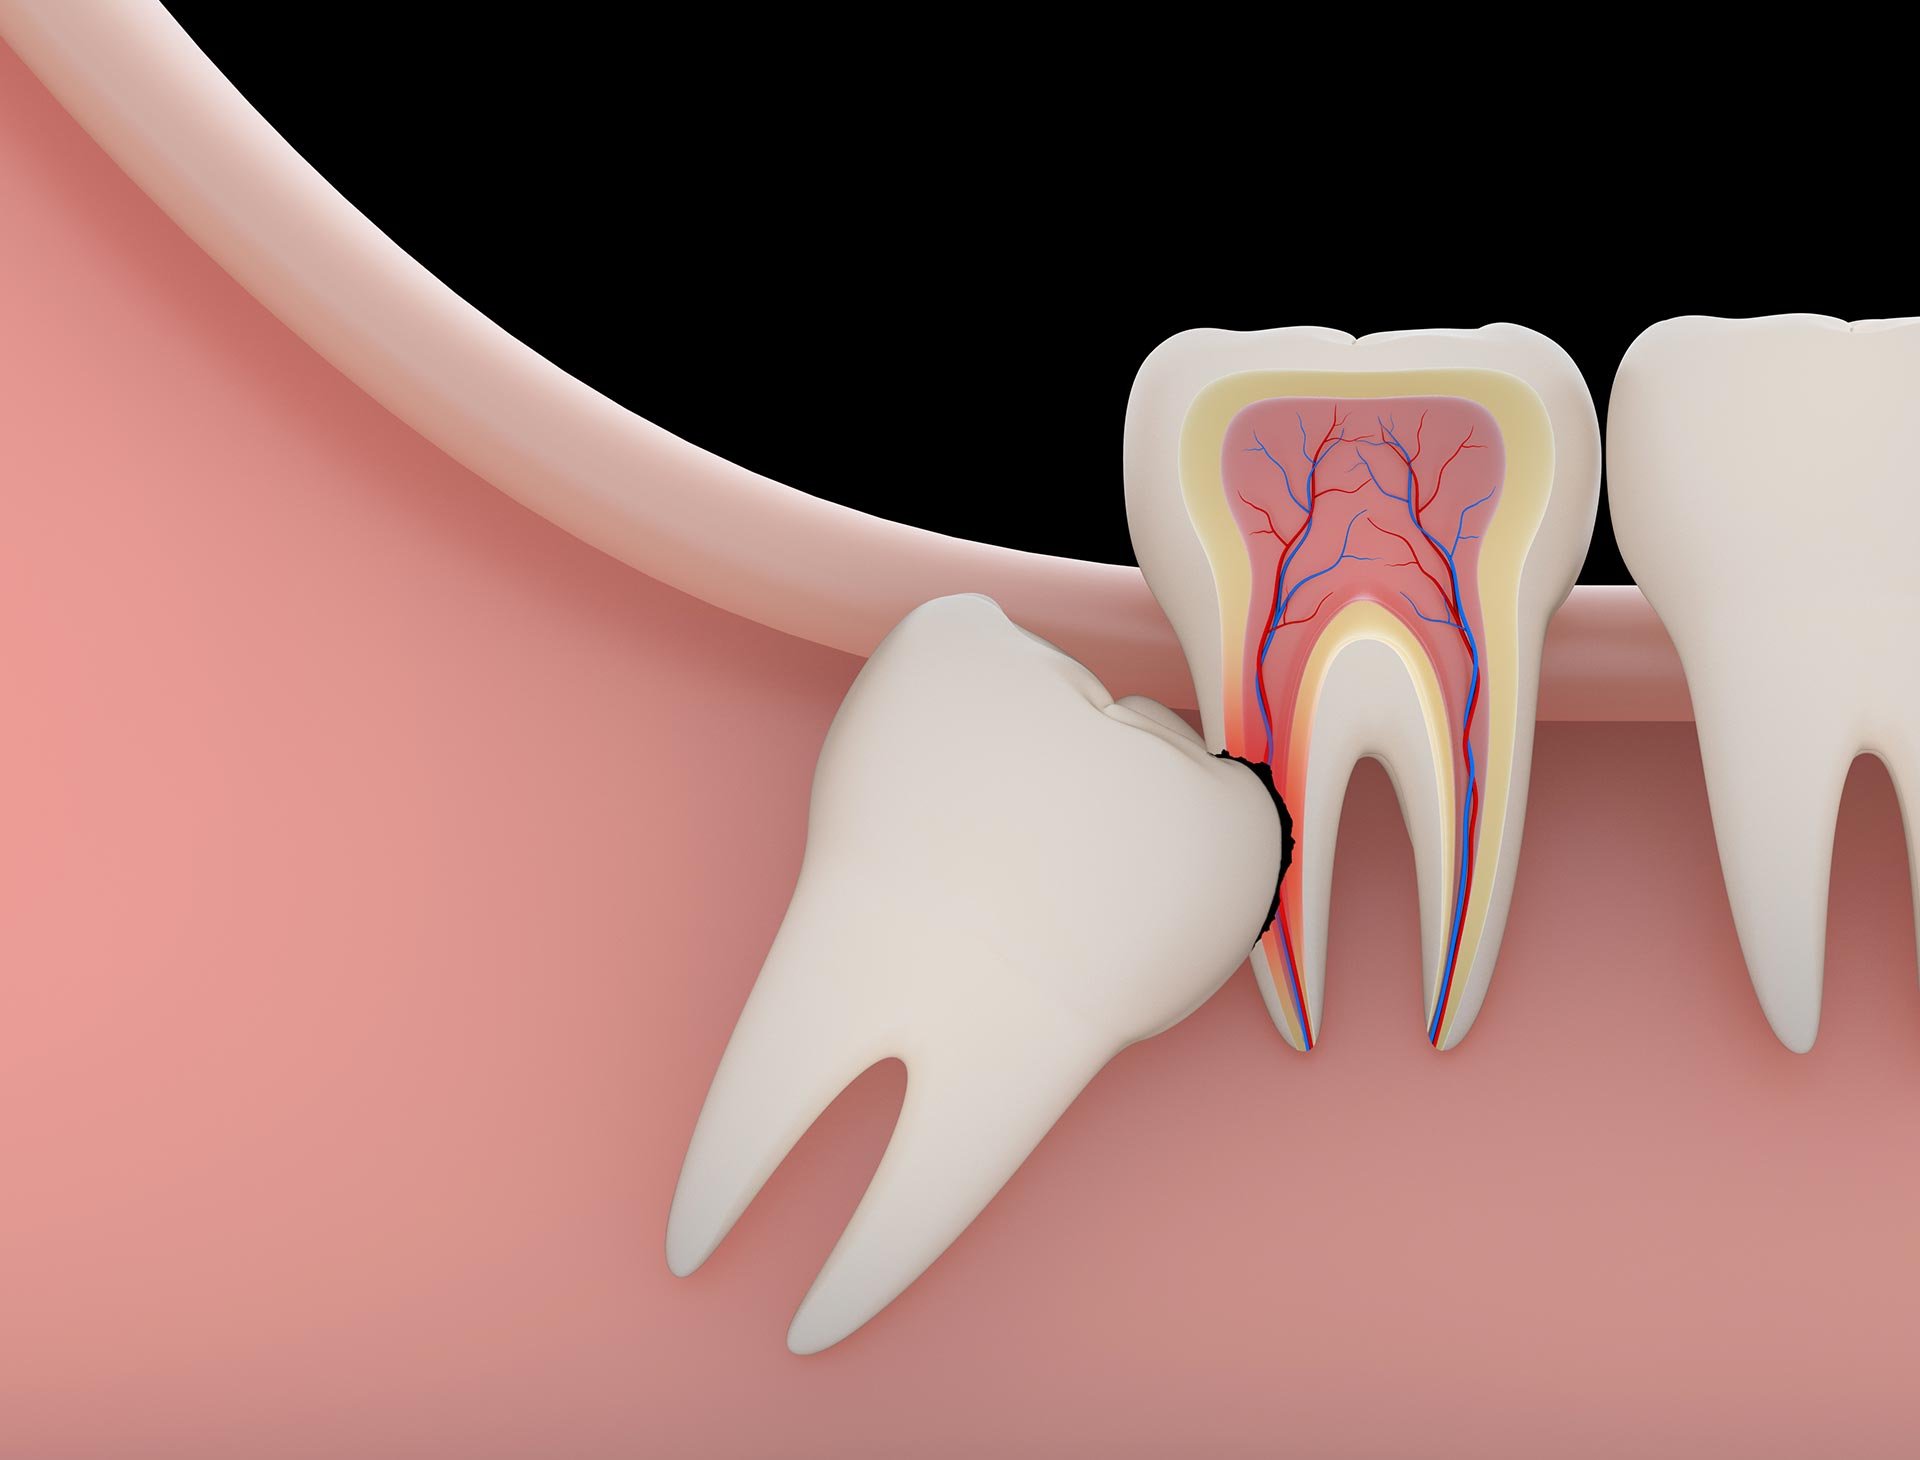

Types of Wisdom Tooth Impactions:

🔹 Soft Tissue Impaction – The tooth is covered by gums.

🔹 Partial Bony Impaction – Part of the tooth is stuck in the jawbone.

🔹 Complete Bony Impaction – The tooth is fully trapped within the jawbone.